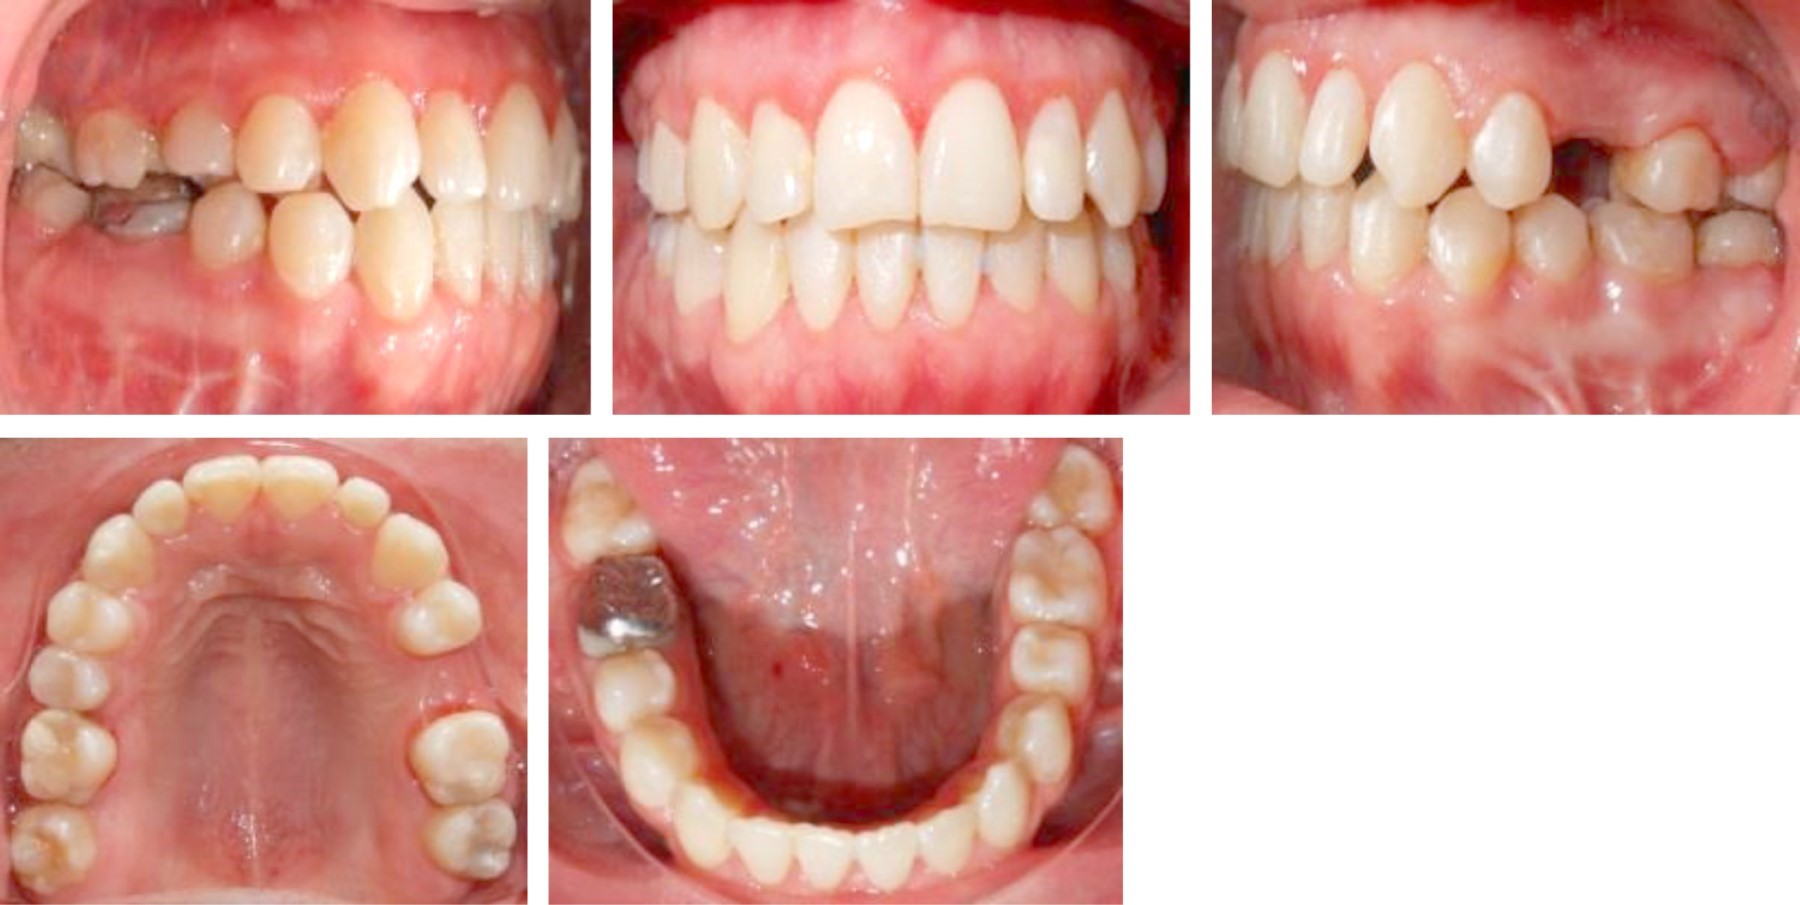

Intraoral characteristics: absence of dental organs 25 and 47, non-coincident dental midlines, square arches, and bilateral class III molar and canine relationship, with an anterior crossbite. Vertical overbite of -3 mm and horizontal overbite of -6 mm (Figure 2).

Orthopantomography was taken to verify radicular parallelism, and control of the osteosynthesis material (Figure 10). The patient continued using elastics to correct muscular patterns of occlusal settlement. Consultation was made with the Department of Periodontics, DEPeI, UNAM, for the future placement of dental implants, where they told us to have an adequate space of 7 mm for the upper left premolar (Figure 11).

The treatment was completed in 23 months, in which the profile was improved, the gingival smile was eliminated, providing facial harmony (Figure 12). The crossbite was eliminated leaving a more stable case, providing an adequate dental harmony, class I canine, and bilateral molar. It was possible to center the dental midlines, improve the shape of the arches, and vertical and horizontal overbite (Figure 13). The dental inclinations were improved and skeletal class I was achieved (Figure 14). A circumferential retainer was placed to improve the occlusal set. After two months, the occlusal adjustment was performed (Figure 15). The changes obtained can be observed facially (Figure 16), occlusally (Figure 17), and radiographically (Figures 18 and 19).

Figure 3

Figure 14